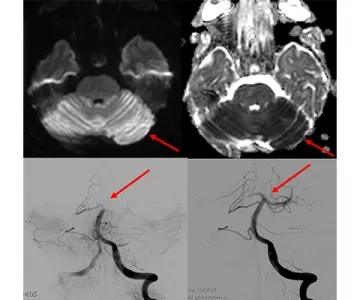

If stroke symptoms have not gone away for more than 6 hours, and if a blockage is detected in one of the main arteries in the brain, interventional radiology comes into play at this point. In the angiography unit, small pipes (catheters) are placed to the clot in the occluded artery in the brain by entering through the groin or the wrist, and the clot is mechanically removed and the blood flow in the occluded artery is restored to normal. When we look at the literature, it has been shown that mechanical removal of the clot, even in periods up to 6-24 hours after the emergence of stroke symptoms, allows the patient to continue his/her life independently or less dependently.

If the acute stroke is treated early, it becomes possible for patients to continue their lives without any disability or addiction. Some of our patients who come with sudden paralysis and speech disorders start to move their arms and legs after the clot is removed while they are still on the angiogram table, and their speech improves, they ask us questions, answer our questions, and return to work within a few days. These situations and moments we encounter in treatment are really pleasing.